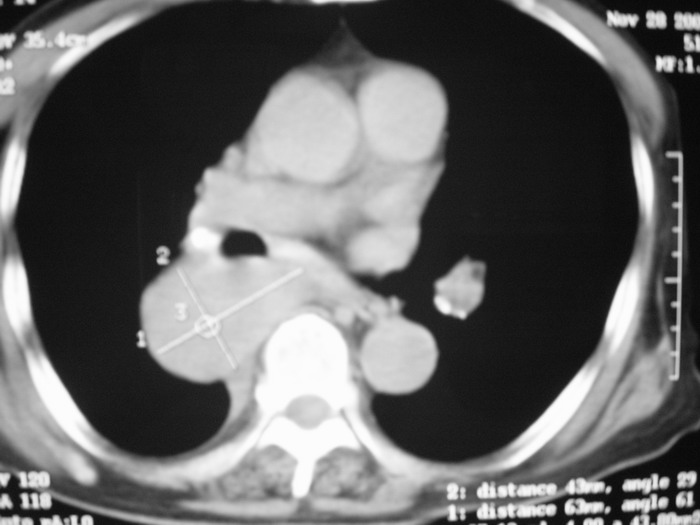

m、70y,反复咳嗽2月。请各位同仁给定位1、(肺?,纵隔?)2、定性。感谢!!

右后纵隔良性占位性病变,神经原性肿瘤可能性大,就其形态看,高密度囊肿待排,建议mri检查。

正位看,支气管分叉角度增大,来源考虑后纵隔的占位,性质考虑1.神经源性肿瘤2.肿大淋巴结

右下肺纵隔旁较大 均匀密度肿块,部分边缘植入纵隔,气管明显受压 变形。支持:后纵隔肿瘤!首选:神经源性!不支持肺内肿瘤原因:1 肿瘤位于下叶支气管及背段支气管开口区,但未侵犯支气管,只是受压表现。2 纵隔内未见肿大淋巴结。3 肺内未见阻塞性肺炎。

支持后纵隔肿瘤,病灶大体呈“滴状”与支气管关系密切,考虑:1.高密度支气管囊肿,2.神经纤维瘤。增强有鉴别意义。